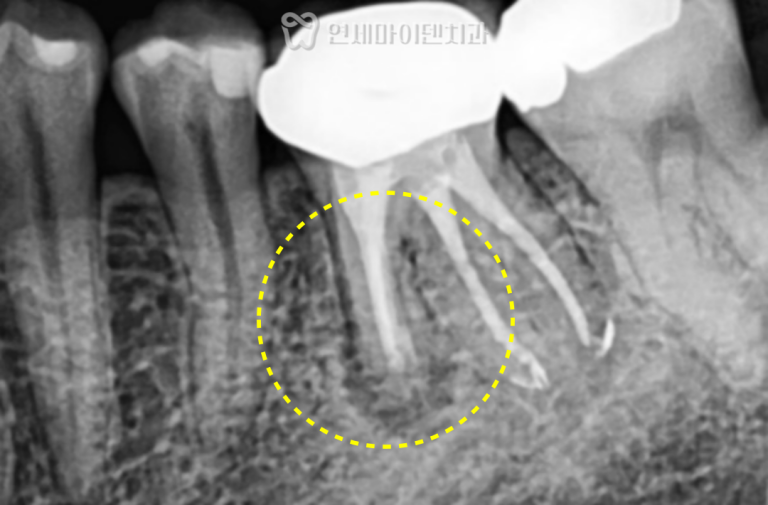

환자분의 왼쪽 아래 어금니(#36)는

기존 금 인레이 아래로 2차 충치가 발생한 상태였습니다.

통증이 동반되었으며, 충치 깊이가 신경에 도달해

신경치료가 불가피한 상황이었습니다.

신경치료를 통해 염증 부위를 제거하고,

레진으로 내부를 밀봉한 뒤 크라운을 수복했습니다.

치근까지 염증이 진행되기 전 내원하신 덕분에

발치 없이 치아를 보존할 수 있었습니다.

조기 내원의 중요성이 잘 드러난 케이스입니다.